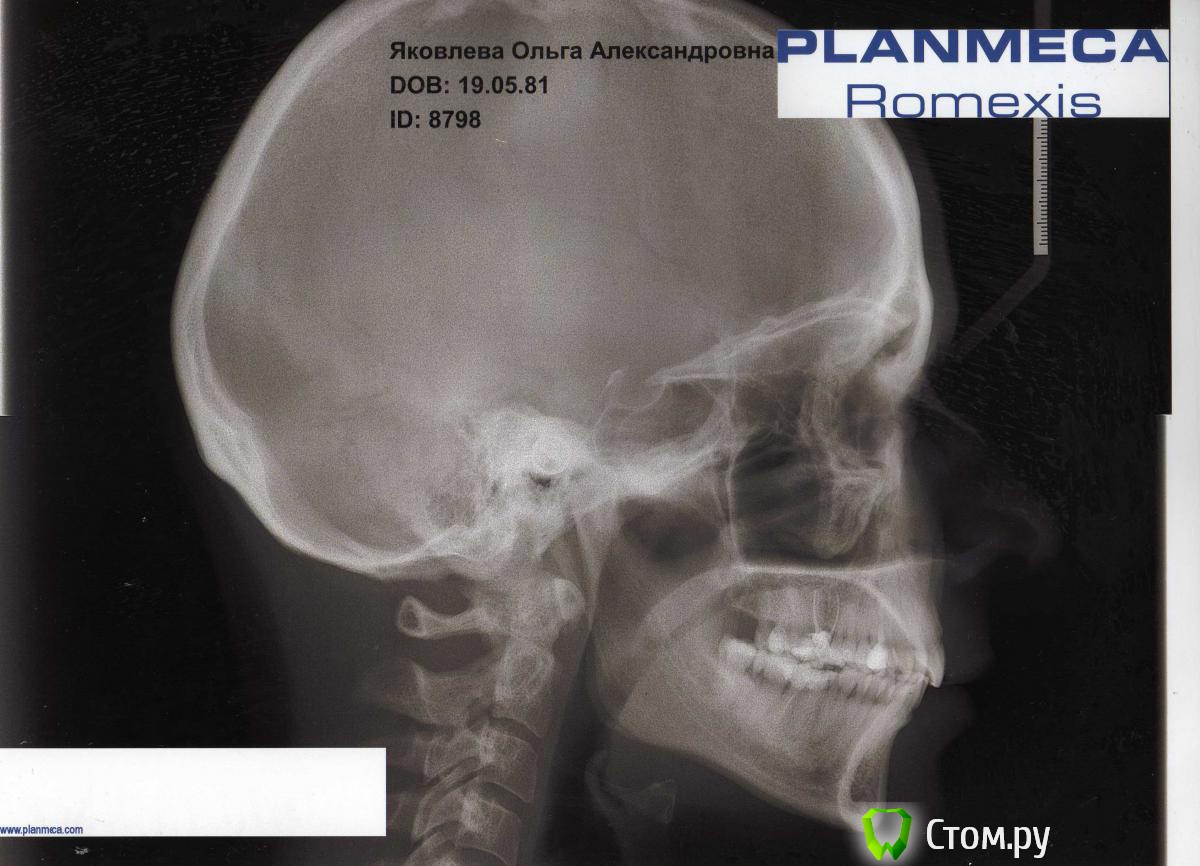

ОлиЯ Опубликовано 13 февраля, 2014 Поделиться Опубликовано 13 февраля, 2014 Была у ортодонта.Сказал не чего не нужно лечить.только удалять 6 снизу. Ссылка на комментарий